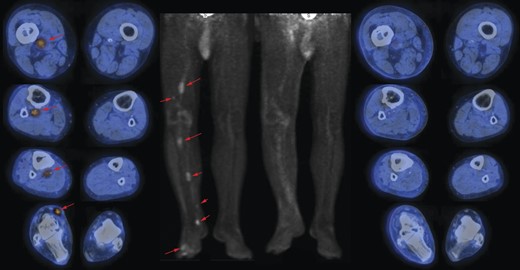

On the left side: images (transaxials fused and maximum intensity projection) of pre-HILP 18F-fluorodeoxyglucose (18F-FDG) PET/CT showing areas (red arrows) of increased uptake representing in-transit metastases in the right lower limb, extending to the thigh; on the right side: images (transaxials fused images and maximum intensity projection) of post-HILP showing clear reduction of pathological uptake of 18F-FDG.